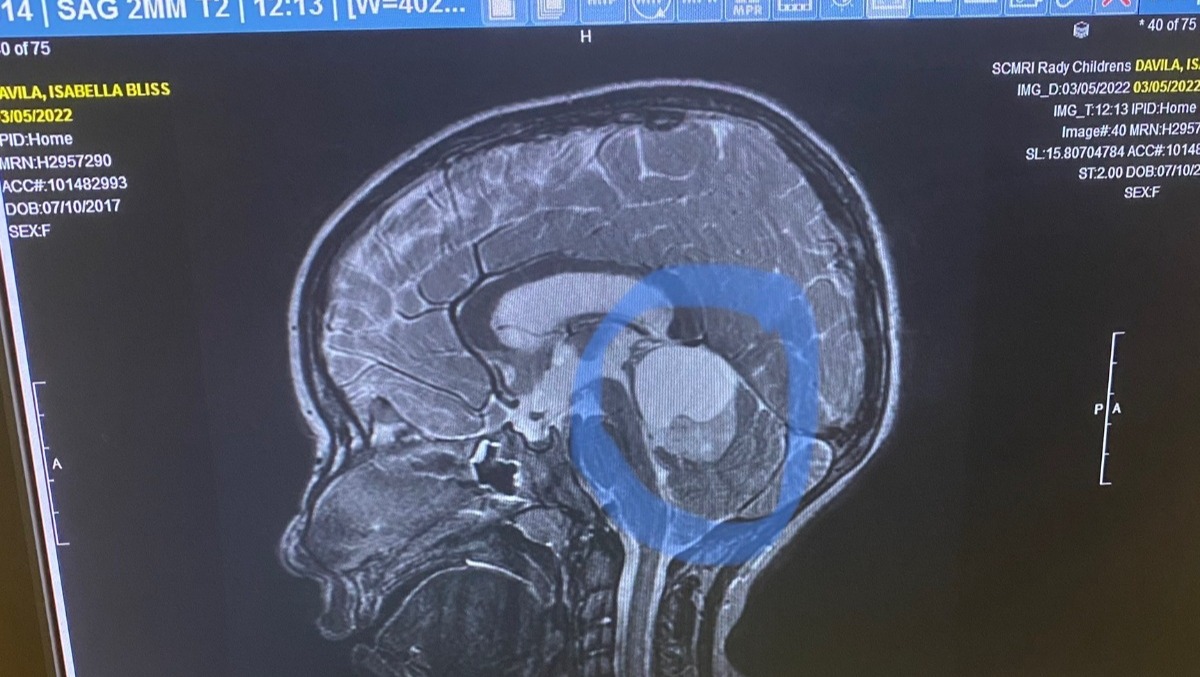

In March 2022, what started as headaches quickly progressed into acute pain, vomiting and popped eye blood vessels. This turned out to be a 3.9cm Pilocyticastrocytoma tumor situated along her brain’s superior cerebellum in the area of the pineal gland. The location of the tumor was blocking cerebral spinal fluid, causing the pressure and symptoms to worsen.